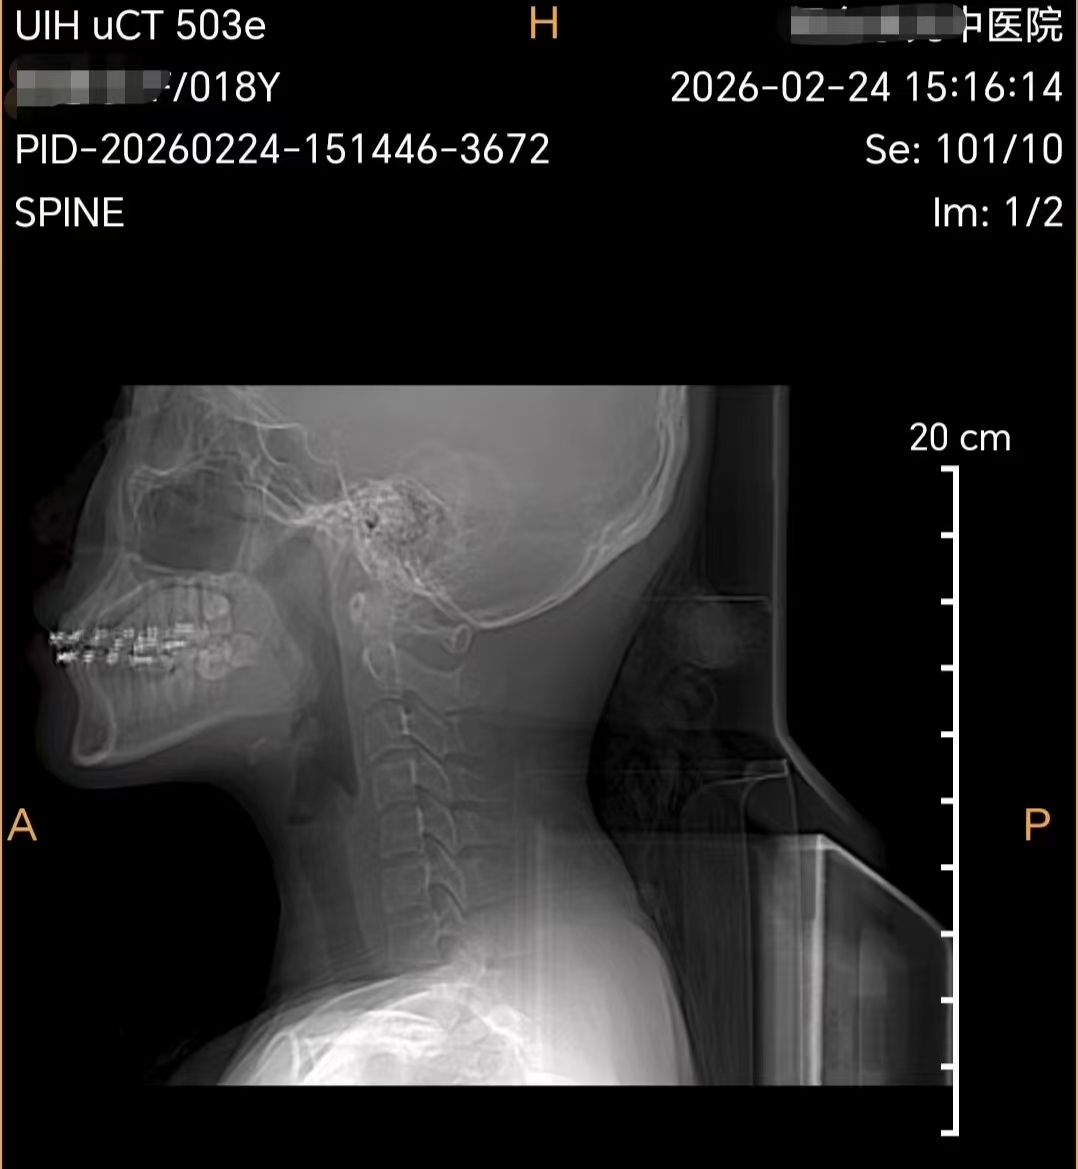

拍片显示,这名18岁的少年颈椎退化犹如50岁中年人状态。理疗科医生表示,青少年骨骼肌肉尚未发育成熟,春节假期里,不少孩子抱着手机、平板度过全天,长时间低头、坐姿歪扭,缺乏运动,导致颈肩僵硬、转头困难,甚至出现头晕、头痛、手麻等症状,部分青少年还查出颈椎生理曲度变直、肌肉严重劳损。“这种长期不良姿势造成的伤害,比成年人更深,要是拖延不治,很容易影响体态和生长发育,留下长期隐患。”